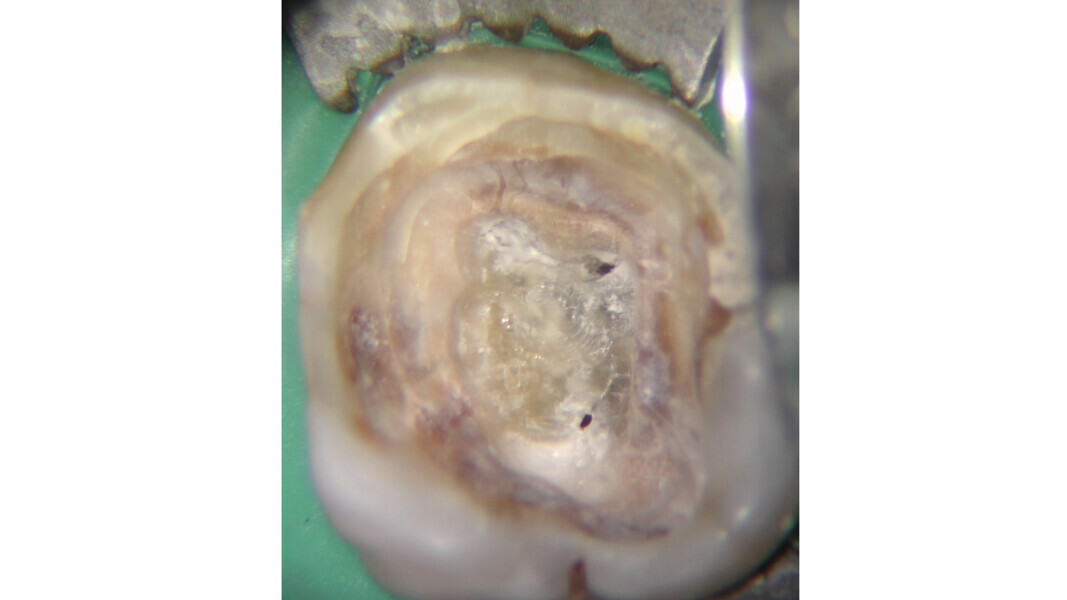

- Loi du changement de couleur : la couleur du plancher de la cavité pulpaire est toujours plus sombre que celle des parois qui lui sont adjacentes.

- Loi de localisation des orifices n° 1 : les orifices des canaux radiculaires sont toujours localisés à la jonction des parois et du plancher de la cavité pulpaire.

- Loi de localisation des orifices n° 2 : les orifices des canaux radiculaires sont localisés dans les angles de la jonction des parois et du plancher de la cavité pulpaire.

- Loi de localisation des orifices n° 3 : les orifices des canaux radiculaires sont localisés à l’extrémité des lignes de fusion développementales de la racine.

La loi du changement de couleur peut être utile lors de l’approche des canaux calcifiés, puisque le praticien peut constamment distinguer les parois plus claires de la cavité pulpaire du plancher plus sombre et donc, rechercher les orifices dans cette dernière zone. Cette caractéristique est constante et sert de guide durant l’exploration des dents sclérotiques.